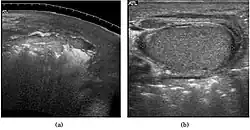

Epididymo-orchitis in a 77-year-old man. (a) Transverse sonography shows enlargement of the epididymis with hypoechogenicity noted over the testis and epididymis associated with scrotal wall thickening. (b) Color Doppler sonography showed hyperemic change of the testis and epididymis, presenting as an “inferno” vascular flow pattern.

Epididymitis and epididymo-orchitis are common causes of acute scrotal pain in adolescent boys and adults. At physical examination, they usually are palpable as tender and enlarged structures. Clinically, this disease can be differentiated from torsion of the spermatic cord by elevation of the testes above the pubic symphysis. If scrotal pain decreases, it is more likely to be due to epidiymitis rather than torsion (Prehn's sign). Most cases of epididymitis are secondary to sexually transmitted disease or retrograde bacteria infection from the urinary bladder.[6] The infection usually begins in the epididymal tail and spreads to the epididymal body and head. Approximately 20% to 40% of cases are associated with orchitis due to direct spread of infection into the testis.

At ultrasound, the findings of acute epididymitis include an enlarged hypoechoic or hyperechoic (presumably secondary to hemorrhage) epididymis [Fig. 20a]. Other signs of inflammation such as increased vascularity, reactive hydrocele, pyocele and scrotal wall thickening may also be present. Testicular involvement is confirmed by the presence of testicular enlargement and an inhomogeneous echotexture. Hypervascularity on color Doppler images [Fig. 20b] is a well-established diagnostic criterion and may be the only imaging finding of epididymo-orchitis in some men.